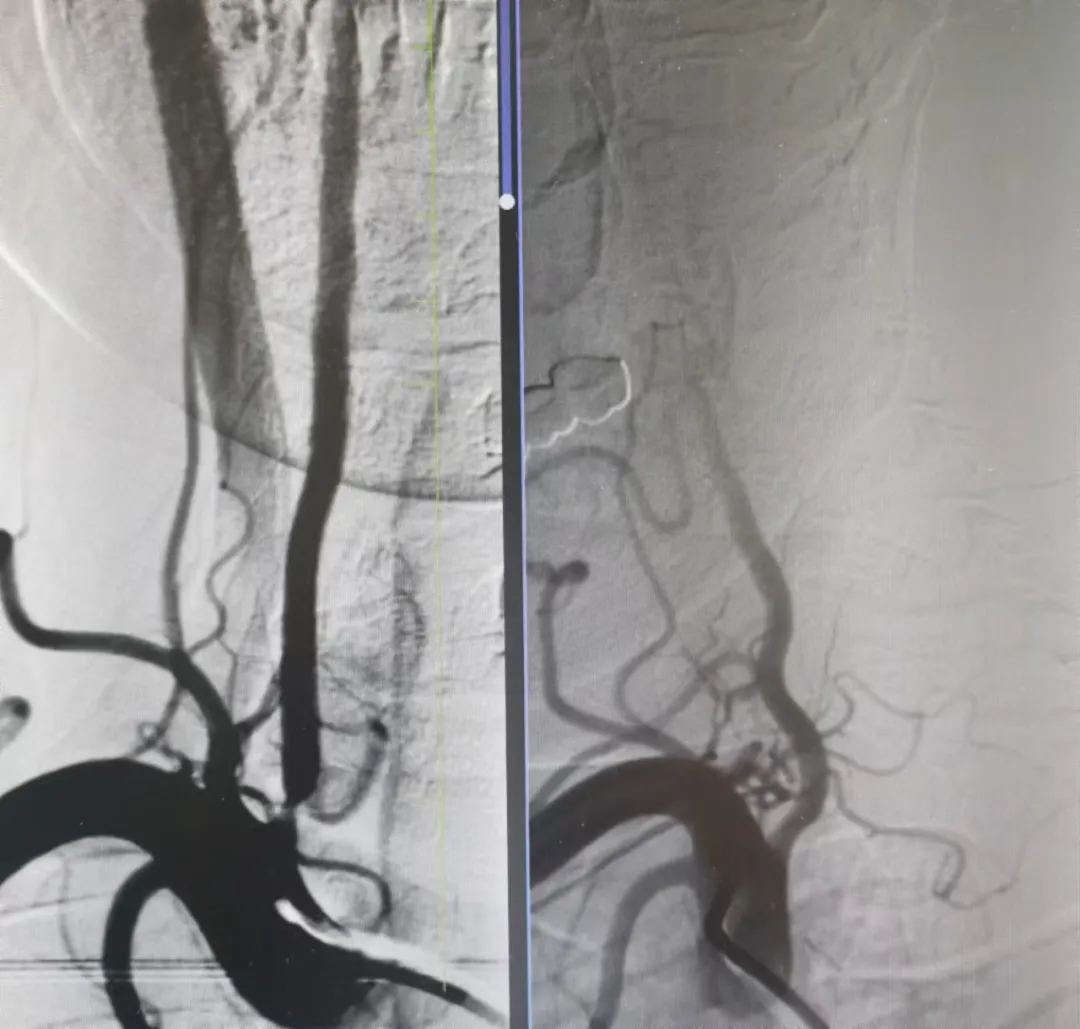

打通腦血管狹窄患者生命線丨國文醫(yī)院一天完成多例神經(jīng)介入手術(shù)

近日,國文醫(yī)院神經(jīng)介入科團隊在丁金明主任和朱洪波副主任帶領(lǐng)下成功為兩例腦血管狹窄患者開通幾近閉塞血管得到患者和家屬一致好評該項技術(shù)自開展以來已為本地區(qū)眾多腦動脈狹窄患者帶來福音 閱讀量:2701